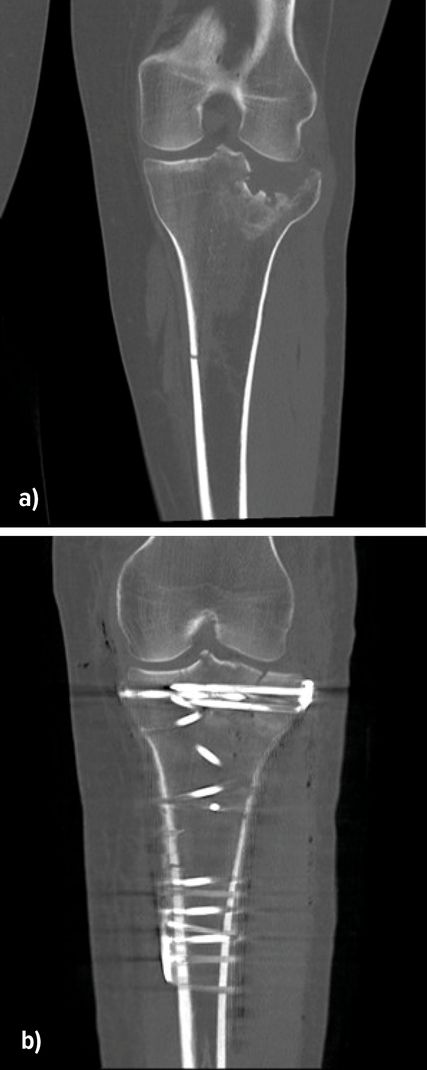

Bei stark geschwollenen Weichteilen ist ein zweizeitiges Vorgehen mit primärer Anlage eines gelenkübergreifenden Fixateur externe für 5–10 Tage erforderlich, um die Weichteile zur Ruhe kommen zu lassen und das Risiko für Wundheilungsstörungen zu senken (Abb.4).

Abb. 4: Anlage eines Fixateur externe bei Weichteilkomplikation und anschließende Versorgung mit einer Platte